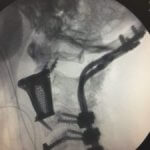

Während einer 10-stündigen Operation ersetzten Chirurgen des Medanta-The Medicity Krankenhauses im indischen Gurugram die beschädigten ersten, zweiten und dritten Wirbel durch jeweils ein 3D-gedrucktes Titan-Implantat. Dadurch konnte die Lücke zwischen dem Schädel und der Wirbelsäule geschlossen werden. Es war der Patientin so wieder möglich, zu stehen und zu Fuß zu gehen. Dieses Verfahren wurde in Indien zum ersten Mal durchgeführt. Zuvor fanden solche Operationen nur in China und in Australien statt.

Der Global Health Care Mitarbeiter in Neu-Delhi, Sanjay Kumar Pathak, erwähnte, dass das 3D-Implantat in seinem Unternehmen entworfen wurde und dann von einer Dienststelle, die SLM Solutions 3D-Drucker nutzen, hergestellt wurde. Als Grundlage für die Implantate dienten CT- und MRT-Bilder, auf deren Grundlage unter anderem ein 3D-Modell der Wirbelsäule gedruckt wurden. So ließen sich die Lücken zwischen den Wirbeln genau ausmessen. An der Entwicklung der 3D-Implantate waren mehrere Designteams aus Indien, den USA und Schweden beteiligt.